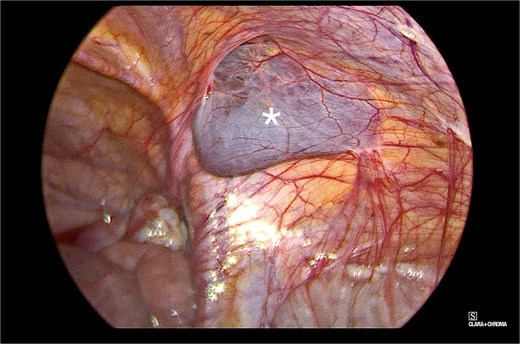

The patient underwent elective diagnostic laparoscopy with hydrocelectomy and mesh hernioplasty. Surgical technique included placement of a 5-mm supraumbilical camera port via open technique with pneumoperitoneum establishment. Two additional working ports were placed bilaterally in the lower abdomen under direct visualization. Diagnostic laparoscopy revealed minimal hemoserous peritoneal fluid and prominent right inguinal swelling confirming the encysted hydrocele (Video 1 and Fig. 5). The peritoneal cavity appeared otherwise unremarkable. A peritoneal flap was created in the right inguinal region, the preperitoneal space was explored, and the encysted hydrocele was carefully dissected and excised without rupture (Fig. 6). The right inguinal region was reinforced with anatomical mesh, and the peritoneal flap was closed.

Intraoperative view of the right inguinal area, demonstrating a bluish-gray, fluid-filled sac (marked with an asterisk in the image). The surrounding structures appeared normal and showed typical anatomy.